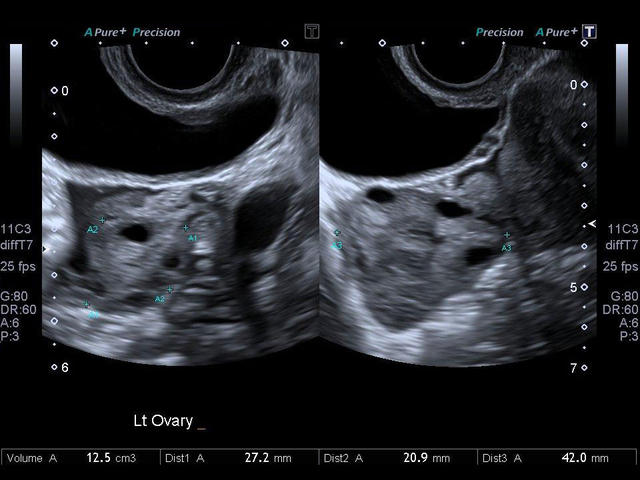

- Гинекология

- Объемная визуализация.

- Полостной конвексный

- Полостной биплановый (конвексный+линейный)

- Превосходное качество изображений и максимальная детализация. Четкое прорисовывание границ и повышенная однородность изображения позволяют без сомнений устанавливать точный диагноз.

- Высокотехнологичное сложное многолучевое сканирование с режимом подавления спекл-шумов в реальном времени - Aplipure plus.

- Одновременная обработка множества смежных ультразвуковых линий Precision Imaging